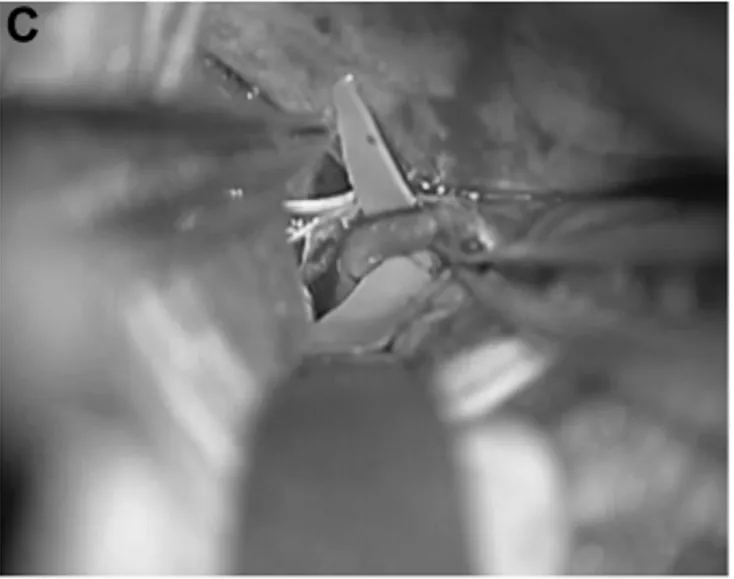

手术实施过程中,专家团队首先通过精准的颞下入路,直达颅内动脉瘤所在位置,避开重要神经与血管分支;随后完成STA-P3血管搭桥,重建颅内远端血液供应,从根源上避免术中及术后脑缺血的发生;再通过动脉瘤孤立术,彻底将病变的动脉瘤与正常脑血管进行隔绝,阻止血流冲击引发破裂。

术中通过吲哚菁绿荧光血管造影反复确认,搭桥血管、P3段及PTA血管保持全程通畅,血液供应正常;随后打开动脉瘤,确认瘤体实现完全闭塞,同时完成血栓切除术,清理瘤体内陈旧血栓。整场手术全程保持精准操作,完美避开颅内关键功能区,未损伤任何神经功能。